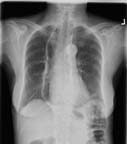

An x-ray image showing perihilar lymphadenopathy in a patient with sarcoidosis.